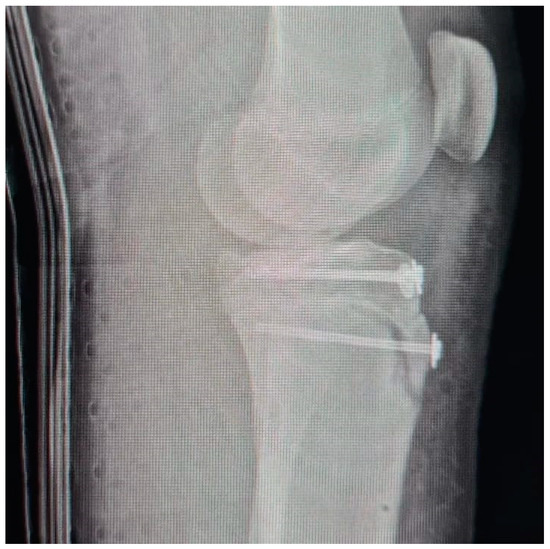

Tibial Tubercle Avulsion Fracture in Young Athletes Surgically Treated: Mid-Long Term Result and Comparison

2.3. Surgical Treatment and Complications